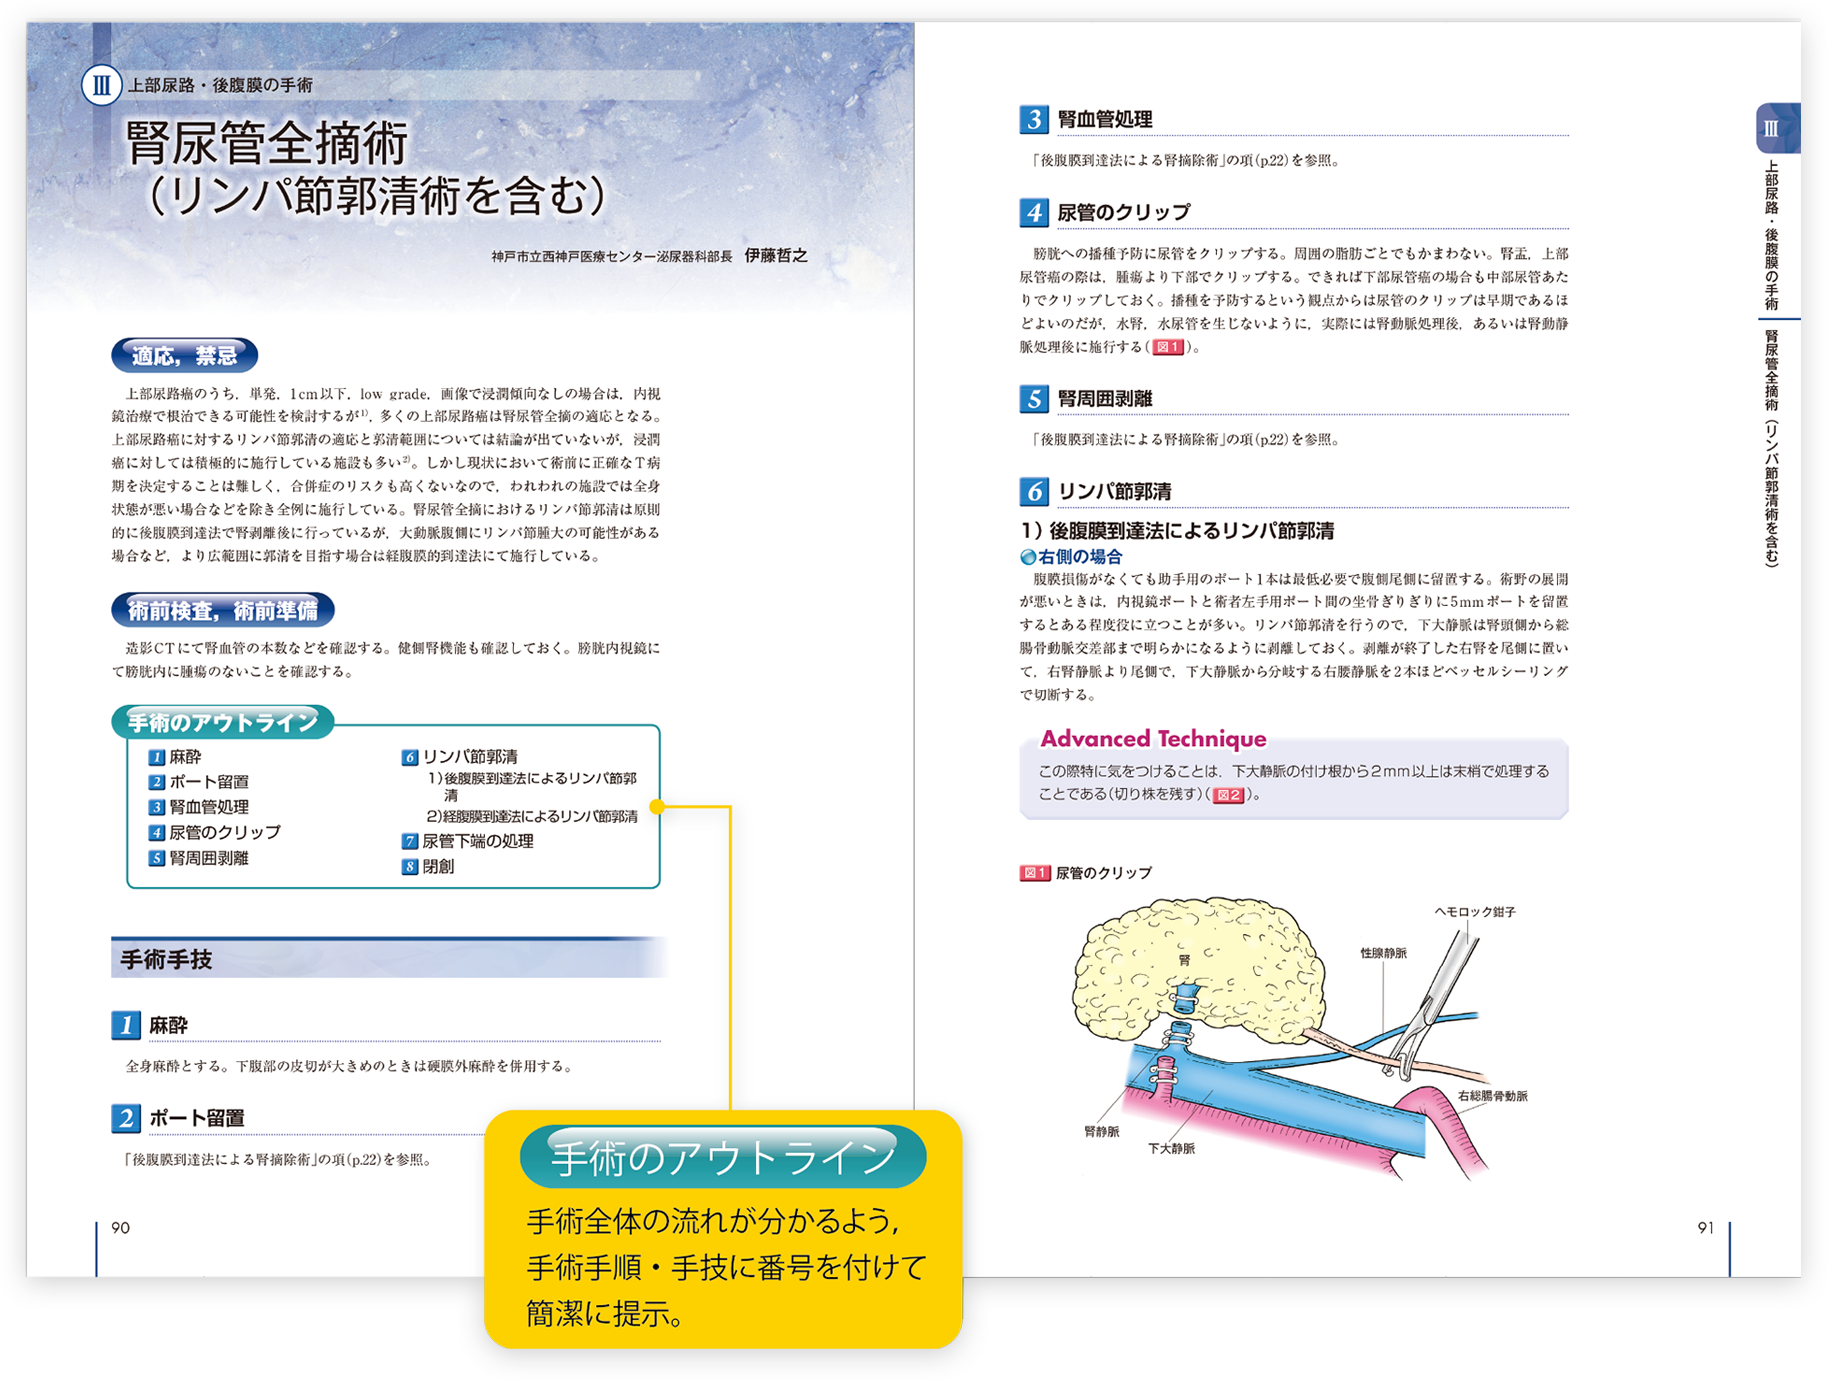

楽天ブックス: 新泌尿器科手術のための解剖学 - 荒井陽一, 図解 泌尿器科手術【電子版】 | 医書.jp,

図解 泌尿器科手術【電子版】 | 医書.jp, メジカルビュー社 | Urologic Surgery Next,

朝倉書店『内科学』(第12版)デジタル付録, Amazon.co.jp: 解剖を実践に生かす 図解 泌尿器科手術 : 影山,

Amazon.co.jp: 解剖を実践に生かす 図解 泌尿器科手術 : 影山, カラー図解 人体の正常構造と機能 第5巻 腎・泌尿器 【改訂第5版